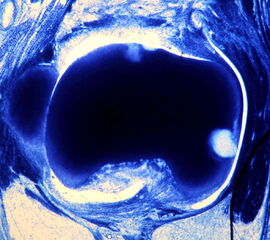

• Hallux valgus interphalangeus (Abb.1, Abb.2)

• Röntgenaufnahme des Fußes (unter Belastung) in dorsoplantarem und seitlichen Strahlengang (Abb. 2a-b).